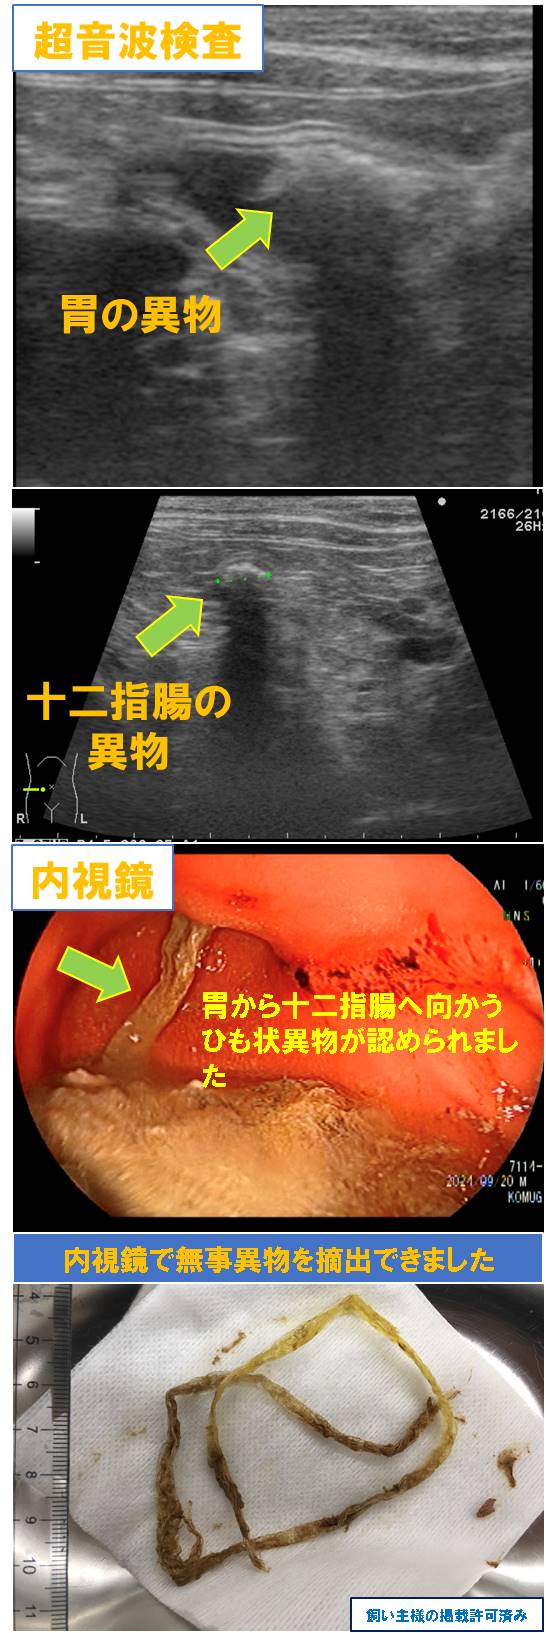

【症例8】「猫 ひも状異物の誤食」

1歳 猫 雑種 オス

一昨日から何回も嘔吐している。吐物に30pのひもがでてきた。

超音波検査で胃から十二指腸にかけて異物が認められました。

内視鏡検査でも胃から十二指腸へ向かうひも状異物を確認しました。

今回は内視鏡で無事ひも状異物を摘出できました。

その後は嘔吐症状は無くなり回復しています